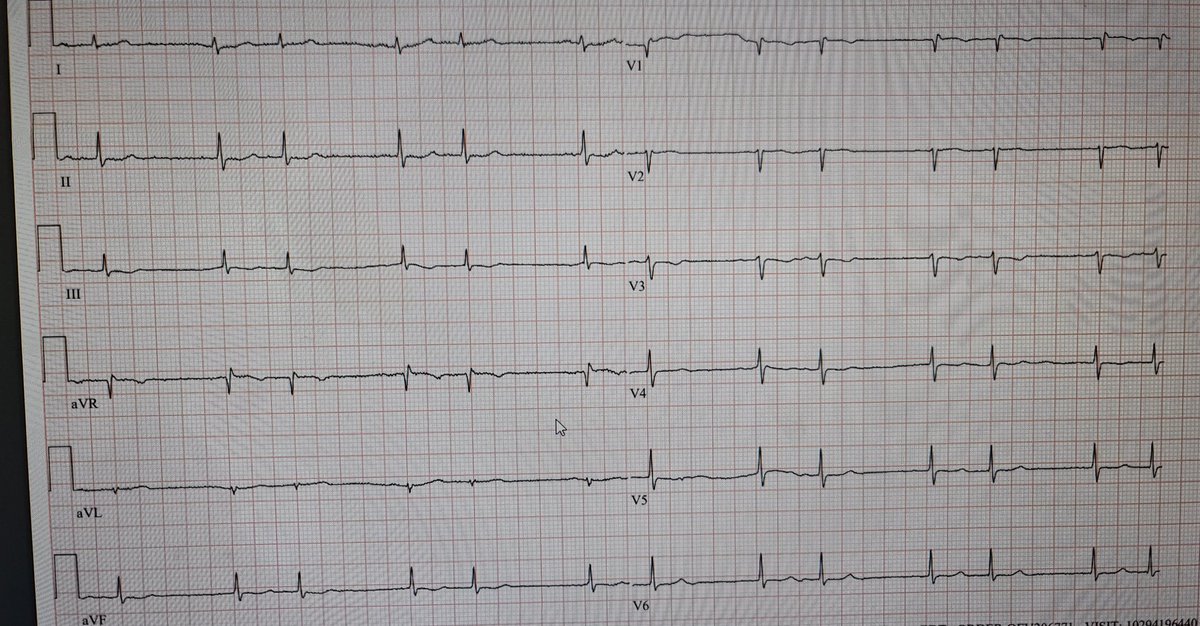

👇Typical Flutter: Quick tricuspid annulus map for diagnosis and ablation success assessment👇